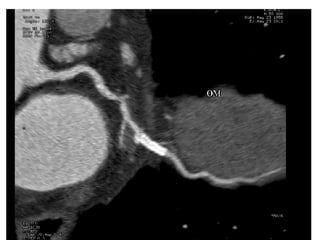

This document contains an ECG test with multiple questions and answers. It discusses cases of: 1. A 60-year-old patient with diabetes, hypertension and chest pain, showing an anterior STEMI with inferior ischemia. 2. A 55-year-old woman with shortness of breath and fatigue, showing a low-voltage ECG and echocardiogram revealing pericardial effusion due to severe hypothyroidism. 3. A 60-year-old with chest pain, showing an anteroseptal STEMI with diffuse ischemia.